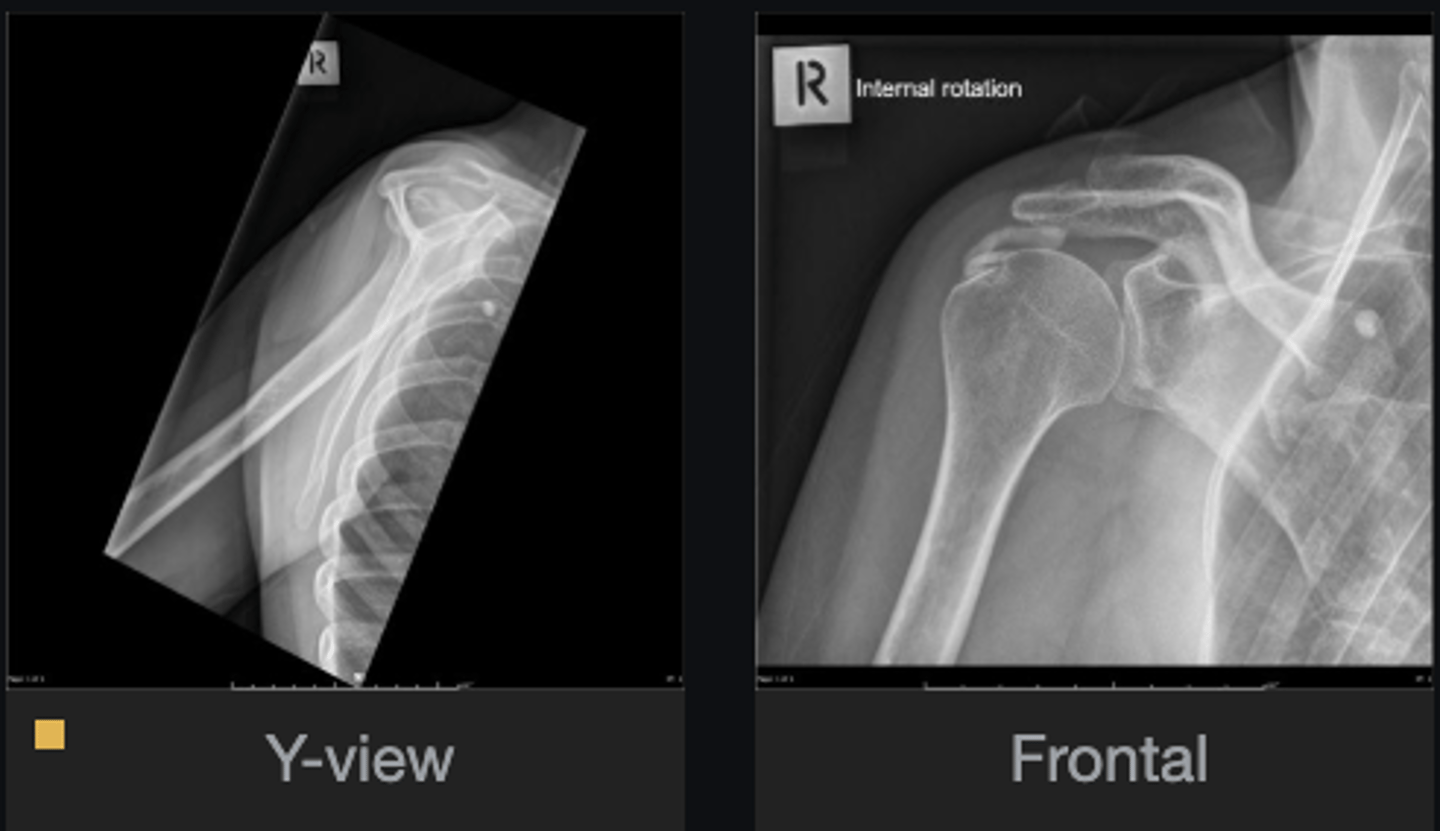

- Increased acriohumeral interval

- Glenohumeral subluxation

- Globular calcification in acromiohumeral interval

List the abnormal findings

Hydroxyapatite deposition disease

Diagnosis?

- Continue chiropractic care as long as patient is improving

- If patient not improving, orthopedic referral

Next step?